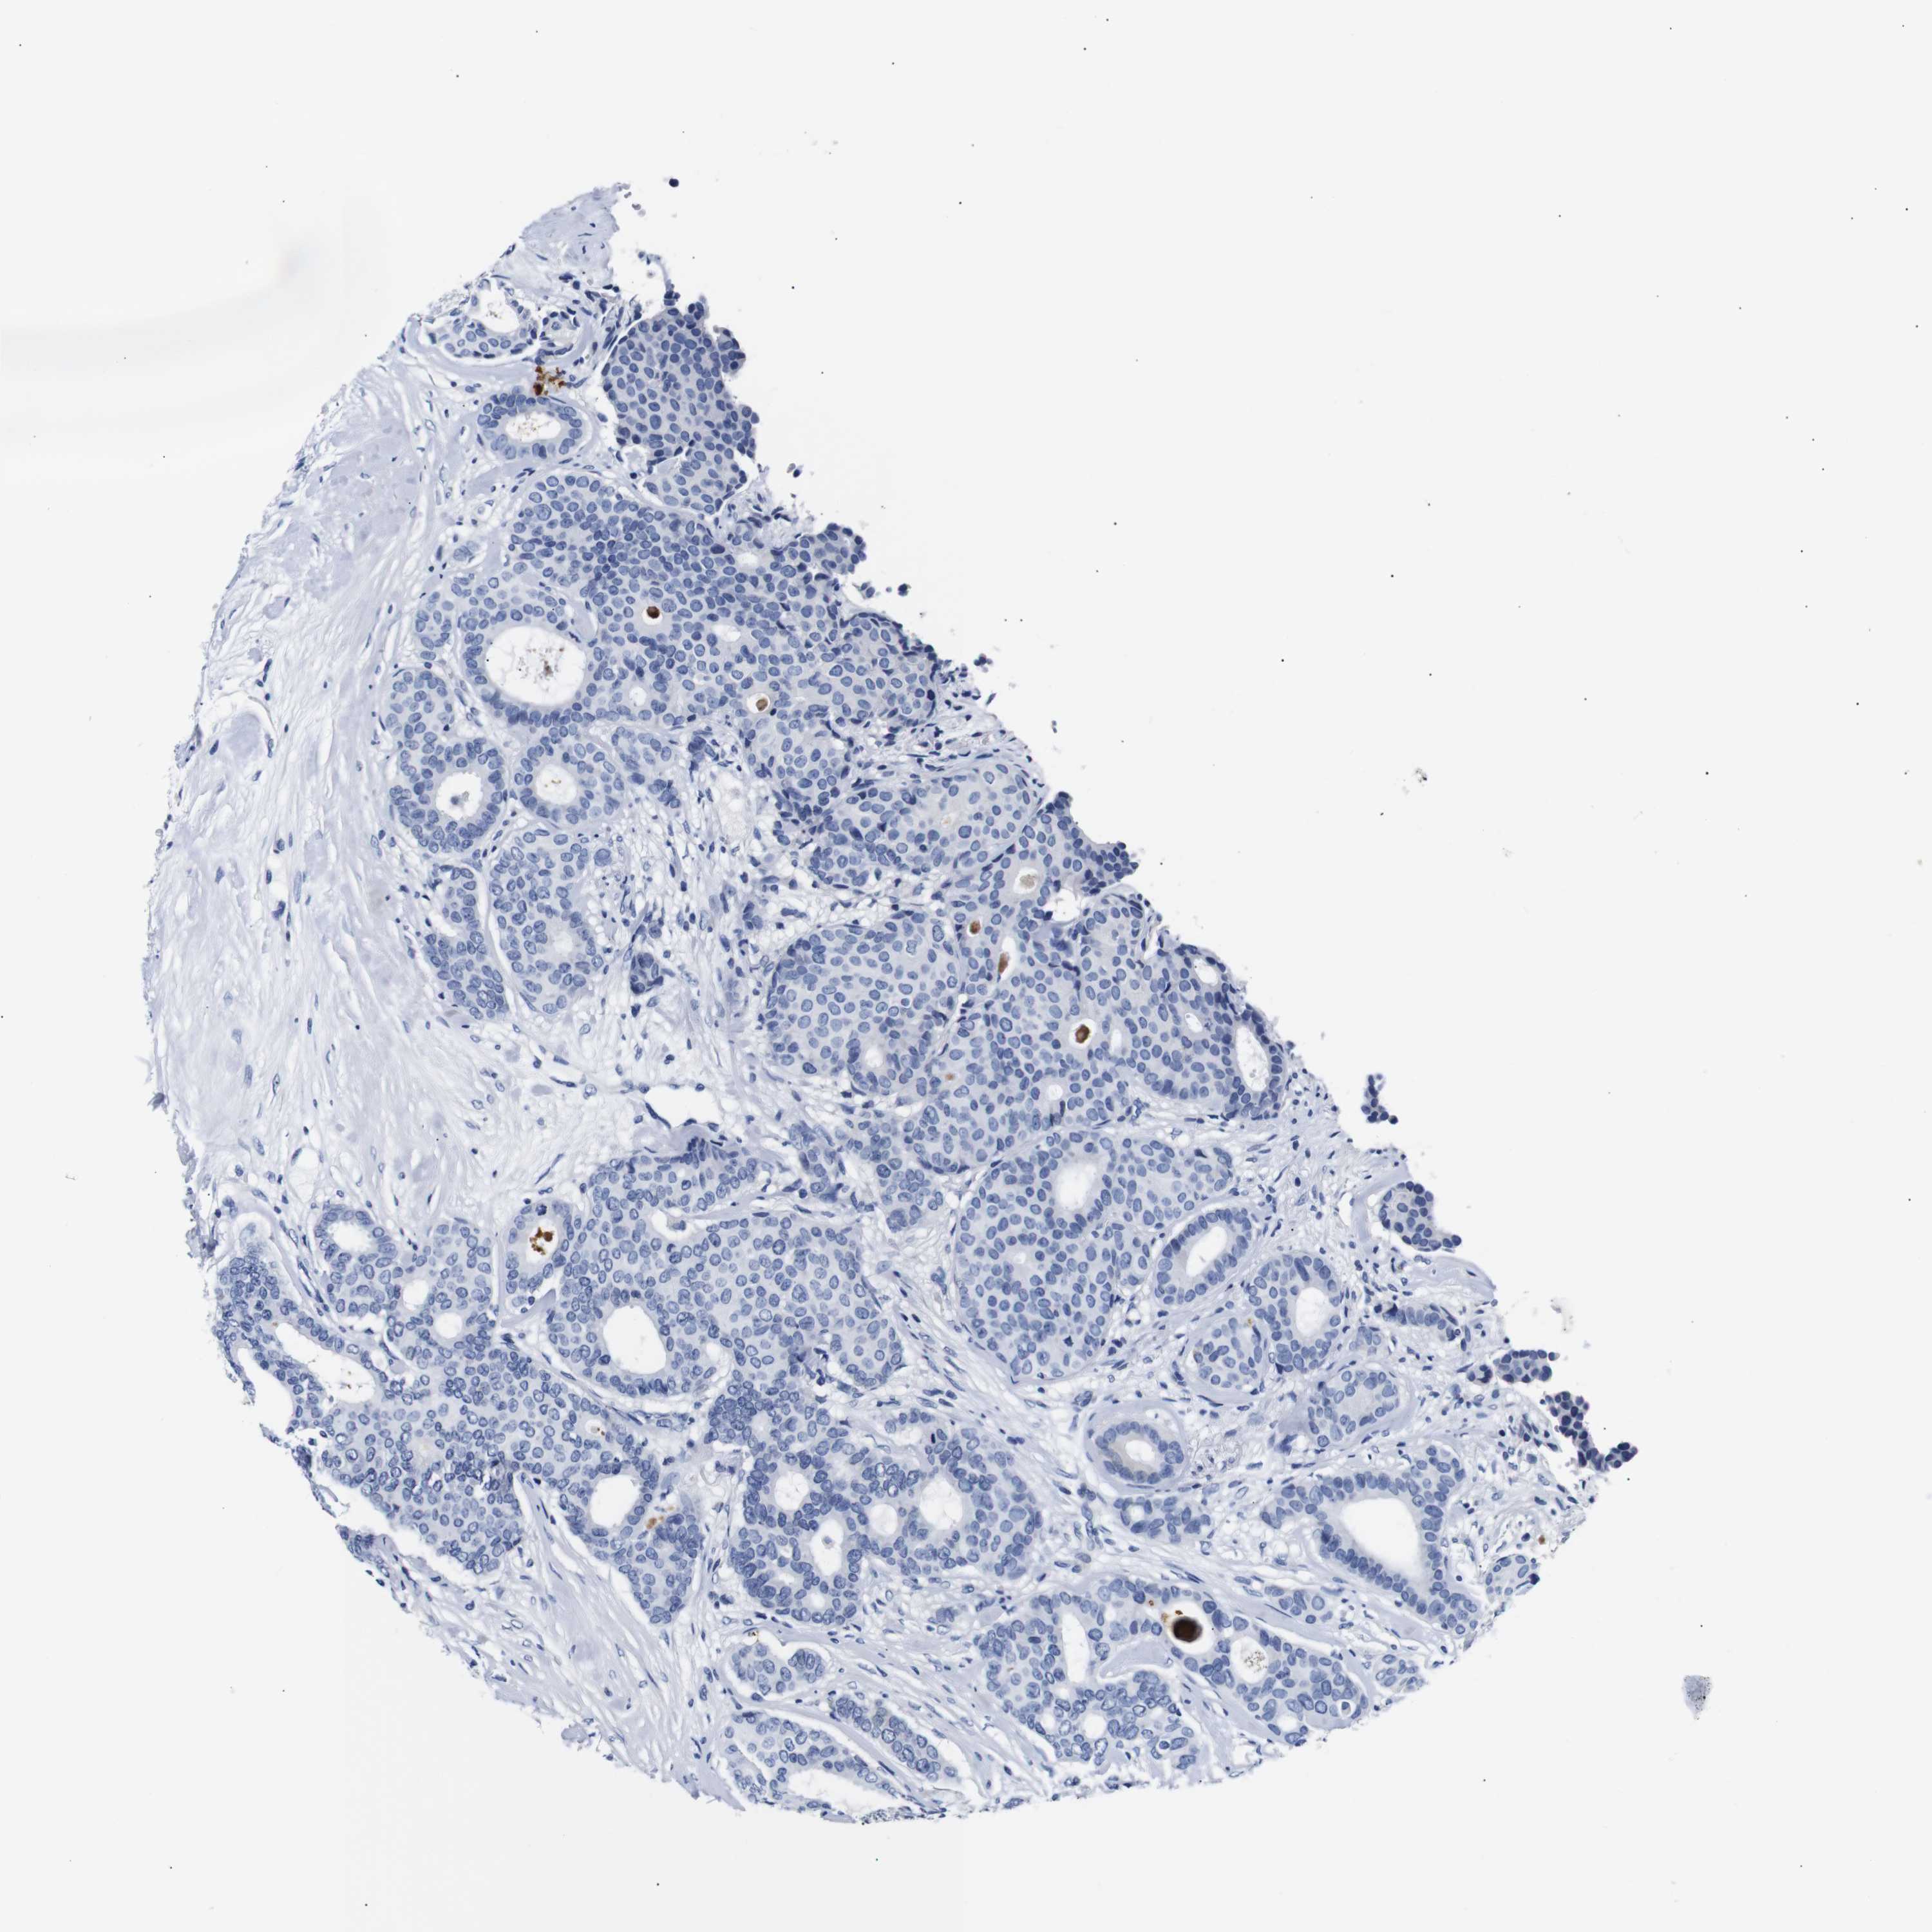

CANCER BREAST CANCER Show tissue menu

Breast cancer

Human cancer